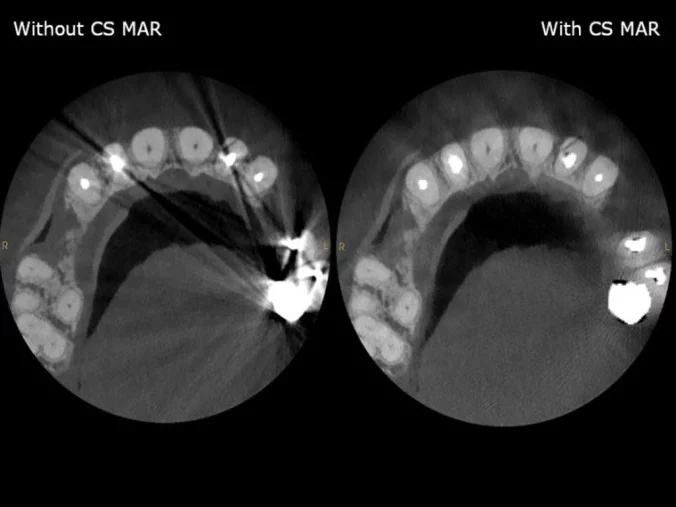

CS MAR

Patentované potlačení artefaktů kovových objektů, umožňující dynamické studium obrazu s filtrem a bez filtru ve vybrané oblasti.